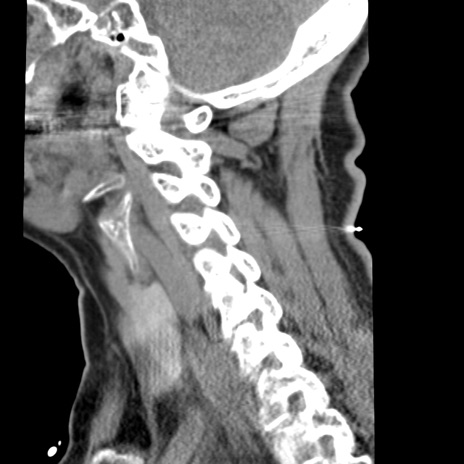

症例50 頚椎CT(矢状断像)

【症例】60歳代女性

【主訴】後頭部〜右後頸部にかけての痛み

【現病歴】本日飲食店でコーヒーを飲んでいたところ、突然後頭部〜右後頸部にかけて痛みが出現し、右上肢の感覚障害を伴ったため救急要請。

【身体所見】脳神経学的に明らかな異常所見を認めず。右上肢に軽度の感覚障害あり。

異常所見と診断は?

頚椎CT